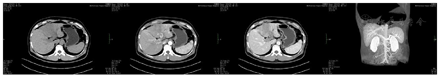

患者心肺无明显异常,腹平坦,右上腹轻压痛,无反跳痛,肝区叩击痛,移动性浊音阴性,肠鸣音正常。实验室检查:甲胎蛋白416.38 μg/ml,异常凝血酶原6 165.31 AU/L,总胆红素42.83μmol/L,AST 65.1 U/L,间接胆红素29.14 μmol/L,乙肝病毒DNA 15 100 U/ml。血常规、凝血功能均在正常范围。腹部CT检查结果:肝脏4段占位,考虑肝细胞癌可能,并门静脉左右主干及左肝内分支多发癌栓形成,门静脉并海绵样变性;左肝多发稍低密度灶,考虑门静脉癌栓,合并小转移灶待排(图1)。MRI检查结果:肝脏4段占位考虑恶性病变:原发性肝细胞癌并门静脉右主、左支及其多发属支癌栓形成;肝门区淋巴结轻度增大。